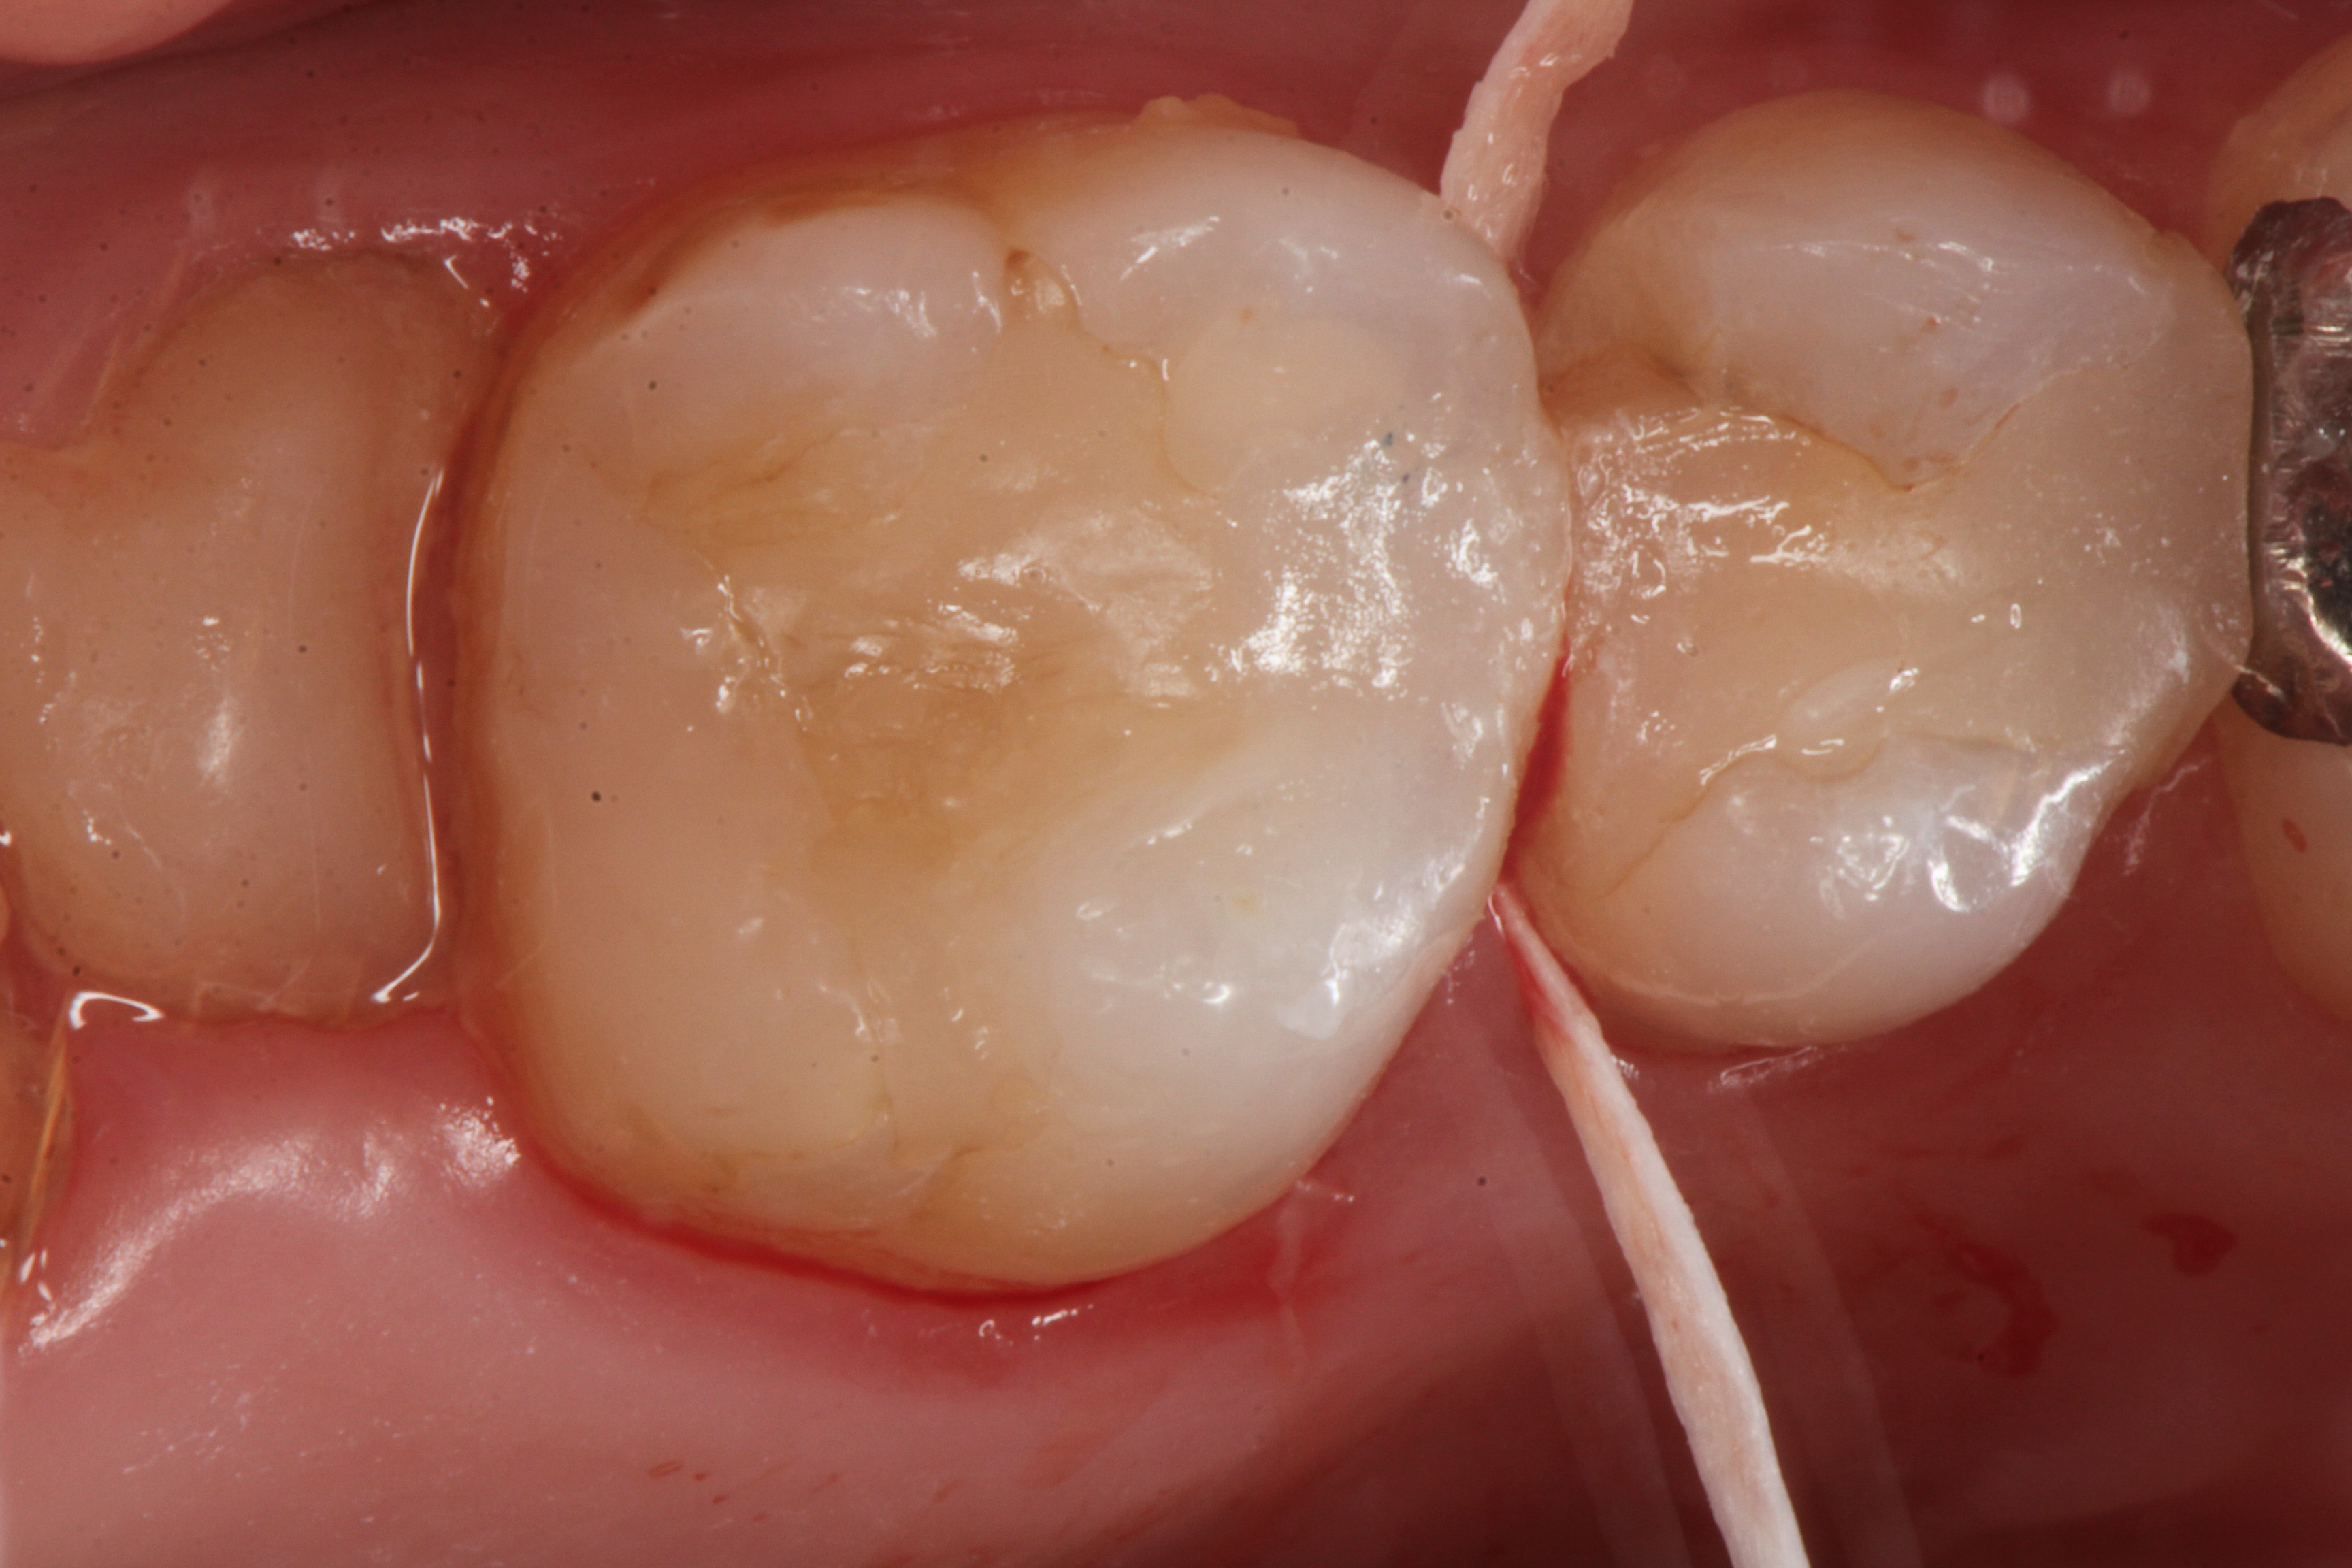

下顎7番の頬側歯茎部カリエスの原因 2025.06.04